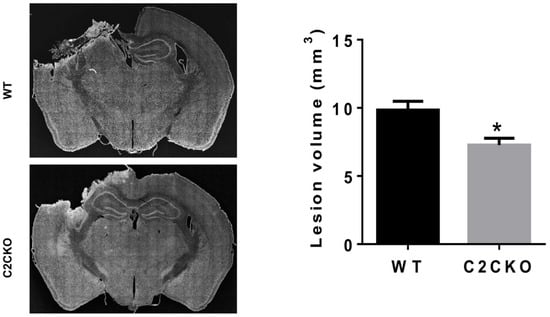

- Wang, Y.; Liu, Y.; Lopez, D.; Lee, M.; Dayal, S.; Hurtado, A.; Bi, X.; Baudry, M. Protection against TBI-induced neuronal death with post-treatment with a selective calpain-2 inhibitor in mice. J. Neurotrauma 2017, 35, 105–117. [Google Scholar] [CrossRef] [PubMed]